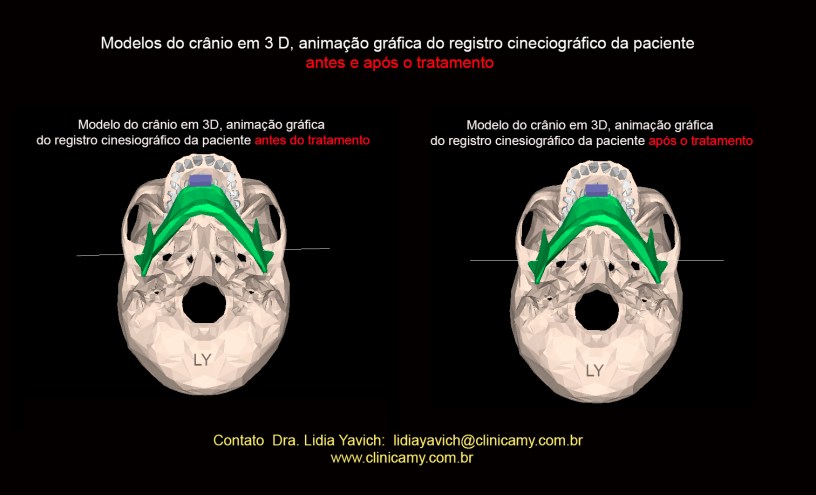

Comparação dos registros cineciográficos da paciente junto com o modelo do crânio em 3 D antes e após o tratamento.

Comparação dos registros cineciográficos da paciente junto com o modelo do crânio em 3 D antes e após o tratamento. Comparação das animações gráficas do crânio em 3 D antes e após o tratamento em abertura máxima.

Comparação das animações gráficas do crânio em 3 D antes e após o tratamento em abertura máxima.